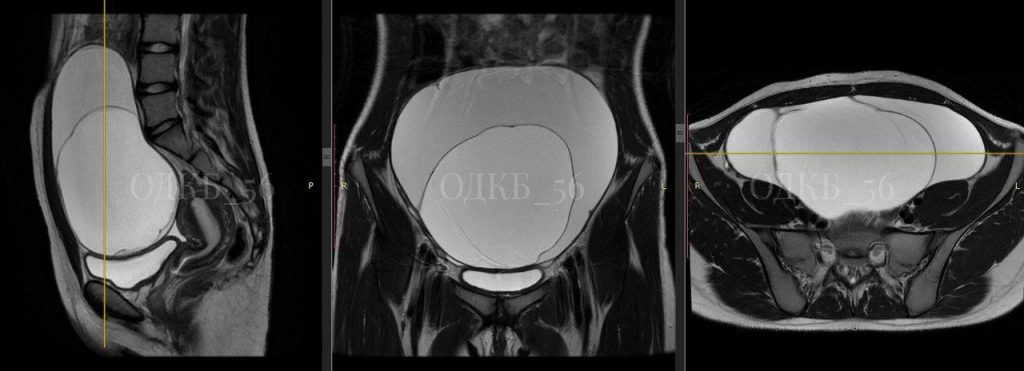

Юная оренбурженка обратилась в экстренное приёмное отделение Областной детской клинической больницы с сильными болями в животе. На УЗИ и МРТ органов малого таза врачи обнаружили новообразование больших размеров. После полного обследования подростку поставили диагноз «муцинозная цистаденома яичника». Хирурги провели сложную операцию и удалили опухоль диаметром 20 см.

— Было подозрение, что образование может стать злокачественным. Ребёнка проконсультировал детский онколог. Учитывая все риски, команда хирургов в срочном порядке выполнила операцию. Образование, исходящее из правых придатков матки, удалили в полном объёме. Сложность вызвали спайки в малом тазу, — рассказала главный внештатный детский гинеколог минздрава Оренбургской области Аниса Гарайс.